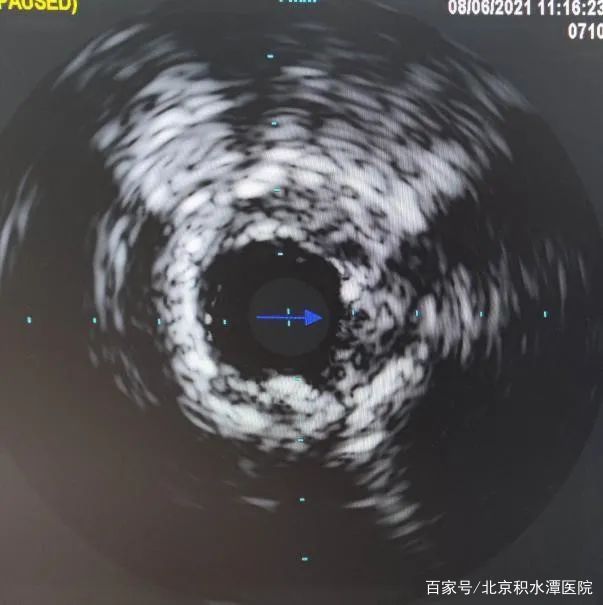

但在上台后,发现3个月过后,左前降支血管已经完全闭塞,手术难度远远超出预期,无法判断血管走行和方向。所以决定采用微量造影剂的办法进行介入治疗。刘教授凭借经验,在只应用少许造影剂的情况下,不断更换导丝进行尝试后,终于通过闭塞病变到达血管远端。导丝通过闭塞病变后,不再使用造影剂,使用IVUS检查发现,闭塞处有严重钙化斑块。通过IVUS明确支架植入位置和大小,最终成功植入支架。手术过程共使用造影剂约20ml。术后监测患者血肌酐,无明显改变并且处于稳定状态。患者也高高兴兴地出院了。

刘巍教授耐心地接诊了病人,阅读患者的病例影像资料后,给患者吃了定心丸, “您放心,我们用冠状动脉的第三只眼来帮助植入支架,可以不用造影剂。” 这第三只眼是什么呢? 是能深入到血管内部看清病变的血管内超声(IVUS),有了血管内超声的指导,不但植入支架更加精准,还可以少用甚至不用造影剂。2021年8月,北京积水潭医院心血管内科刘巍主任带领介入团队在崭新的新龙泽院区导管室,使用最先进的壁挂式血管内超声(IVUS)对严重造影剂过敏的患者以及严重肾功能不全的患者进行了零造影剂或微量造影的冠状动脉介入治疗。帮助患者解决了严重造影剂过敏和严重肾功能不全恶化的问题。

在对李女士的治疗过程中,刘巍教授在患者的第一次冠状动脉造影的影像指导下,经过远端桡动脉入路,将指引导管放置在右侧冠状动脉开口,导丝送至血管远端,但是由于患者病变弥漫,狭窄严重,并且开口就有病变,指引导管稍微深插就会出现压力下降和心电图ST段抬高,手术的难度超出预期。这时使用IVUS进行血管内超声检查,结果显示,右冠状动脉中段最小管腔面积仅2.0mm2,并且可见超声衰减斑块和高负荷脂质斑块,并且病变比预想的还要弥漫和严重。刘教授团队根据边支定位以及IVUS导管标记点定位,对狭窄病变进行充分预扩张,复查IVUS提示扩张效果满意后,根据IVUS定位精准地植入了两枚支架,再次复查IVUS提示支架膨胀及贴壁良好,无边缘夹层等情况。手术过程顺利,全程未使用一滴造影剂就成功完成了支架的植入。术后患者没有出现任何不适。手术过程不到30分钟,患者术后症状立刻缓解。第3天就出院了。

但在上台后,发现3个月过后,左前降支血管已经完全闭塞,手术难度远远超出预期,无法判断血管走行和方向。所以决定采用微量造影剂的办法进行介入治疗。刘教授凭借经验,在只应用少许造影剂的情况下,不断更换导丝进行尝试后,终于通过闭塞病变到达血管远端。导丝通过闭塞病变后,不再使用造影剂,使用IVUS检查发现,闭塞处有严重钙化斑块。通过IVUS明确支架植入位置和大小,最终成功植入支架。手术过程共使用造影剂约20ml。术后监测患者血肌酐,无明显改变并且处于稳定状态。患者也高高兴兴地出院了。